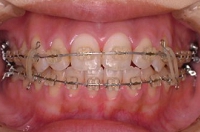

CASE4

前歯で物が噛み切れない。 顔が曲がって見える。

右のアゴが たまに痛い。

(19歳/女性)↓

概要・担当医コメント:

開咬/下顎の左右的偏位/顎関節症/非抜歯

動的治療期間28ヶ月(28回)/費用概算:65万円

顎関節症の改善を主目的として治療を開始しました.歯科矯正用アンカースクリューを使用することにより,上下とも非抜歯で治療出来ました.大臼歯の上下的位置を調整することで,顎関節に負担のかかり過ぎない噛み合わせにしました.